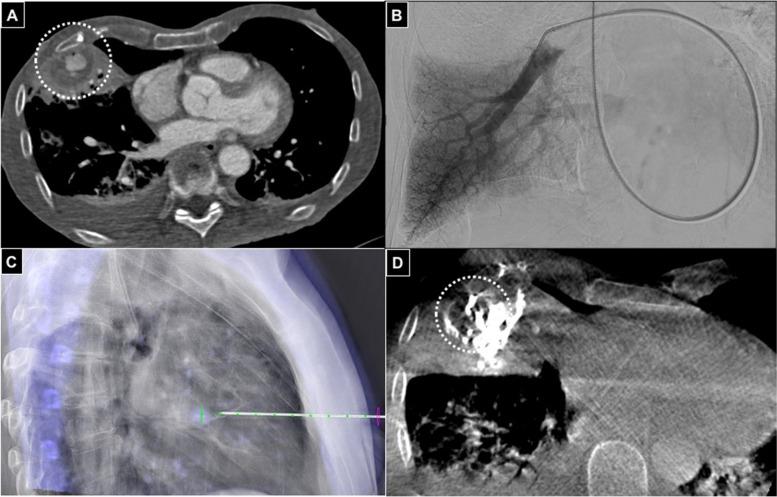

Fifty-four patients data were collected from five centers. All patients at the time of treatment presented with unruptured PAs and were hemodynamically stable. True aneurysms and lesions treated with embolics other than glue were excluded. Pseudoaneurysms diagnosis was based on CT and anamnestic data; initial investigation with digital-subtracted arteriography was acquired in all cases; then, percutaneous embolizations were performed in the angio-suite (ultrasound, fluoroscopy, ConeBeam CT guidance) or in CT. Technical success was considered as complete pseudoaneurysm embolization at final imaging with sole percutaneous strategy, without need for additional endovascular embolization. Clinical success was intended as pseudoaneurysm resolution within one week follow-up with stabilization or restored clinical conditions. Pseudoaneurysms origins were traumatic (57.4%), inflammatory (24.1%) or spontaneous (18.5%); 39 patients (72.2%) were symptomatic, presenting with pain and/or pulsatile mass. Mean lesions diameter was 19.3 mm (range: 7-30); pseudoaneurysms were located in abdomen (48.1%), limbs (42.6%) and thorax (9.3%). Coagulation function was impaired in 16.6% and 48.1% was under antiplatelets/anticoagulation therapy. In 16.6% the percutaneous approach followed previous treatments failure. The image-guidance modality for percutaneous puncture was most often ultrasound combined with fluoroscopy (38%). Clinical success was obtained in all patients while technical success occurred in 94.4% because 3 patients required an additional endovascular embolization. Complications were registered in 14.8%, all of low grade without clinical sequelae neither prolonged recovery (7 non target embolizations, 1 post-embolization syndrome).

从五个中心收集了54例患者的数据。所有患者在治疗时均表现为未破裂的假性动脉瘤,血流动力学稳定。排除真性动脉瘤和用胶水以外的栓塞剂治疗的病变。假性动脉瘤的诊断基于CT和既往病史数据;所有病例均进行了数字减影血管造影的初步检查;然后,在血管造影套件(超声、荧光透视、锥形束CT引导)或CT中进行经皮栓塞。技术成功定义为在最终成像时仅通过经皮策略完全栓塞假性动脉瘤,无需额外的血管内栓塞。临床成功定义为在一周随访内假性动脉瘤消退,临床状况稳定或恢复。假性动脉瘤的起源为创伤性(57.4%)、炎症性(24.1%)或自发性(18.5%);39例患者(72.2%)有症状,表现为疼痛和/或搏动性肿块。病变平均直径为19.3毫米(范围:7-30);假性动脉瘤位于腹部(48.1%)、四肢(42.6%)和胸部(9.3%)。16.6%的患者凝血功能受损,48.1%的患者接受抗血小板/抗凝治疗。16.6%的患者经皮方法是在先前治疗失败后采用。经皮穿刺的图像引导方式最常为超声联合荧光透视(38%)。所有患者均获得临床成功,94.4%的患者获得技术成功,因为3例患者需要额外的血管内栓塞。并发症发生率为14.8%,均为低级别,无临床后遗症,恢复也未延长(7例非靶栓塞,1例栓塞后综合征)。